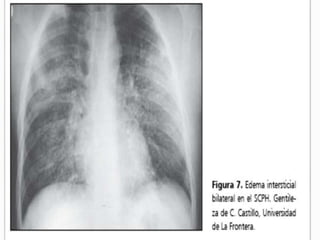

La RX tórax es de utilidad para evaluar las condiciones

cardiacas (forma y tamaño de la silueta cardiaca) y valorar

la congestión pulmonar; como herramienta en el

diagnóstico y seguimiento.